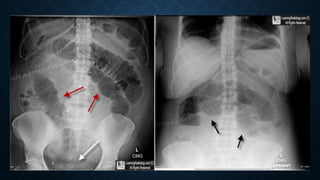

This document provides an overview of x-rays for medical students, covering topics such as ensuring x-rays are well-aligned, exposure levels, common artifacts and anatomical features, abdominal x-ray positions and views, and specialized x-rays including barium swallows, enemas, and tests to examine the esophagus, small bowel, biliary tree, and kidneys.